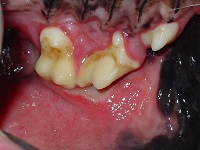

A 6 year-old Cocker Spaniel is presented with halitosis and inappetence, 3months after he

had a professional scale and polish procedure done at your practice. On physical examination

there is lymphadenopathy of the regional lymphnodes and the dog is very painful when you touch his

mouth. A conscious oral examination is impossible. You aneasthetise the animal and see

the following (photo). The ulcerative lesions correspond to the maxillary teeth present in

that area. Apart from the buccal mucosa, the lateral lingual mucosa is also inflamed and

covered by a pseudomembrane.

b) Gingivitis, plaque accumulation (very little calculus present).

c) Ulcerative stomatitis presents in certain breeds like Maltese terriers, Cocker Spaniels,

Maltese poodles and Dacshunds. The typical presentation is of a patient with very little

plaque and hardly any calculus covering the teeth. They present mainly with ulcer opposite

certain maxillary teeth, like the canine, 4th premolar and 1st molar tooth, as well as lateral

borders of the tongue being inflamed. Sometimes they may present with severe stomatitis as

the pictures shown (Photo). The bacterial cultures from these patients show a mixed